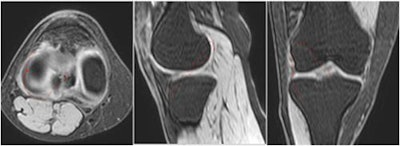

Measurements of graft length on multiplanar reconstruction images (from left to right: axial, sagittal, and coronal planes).The average time it took to process the MRI scans to create the 3D virtual model was 41 minutes and the average time to print the 3D-printed knee was 11 hours. The cost of the materials used to make each model was approximately four euros.